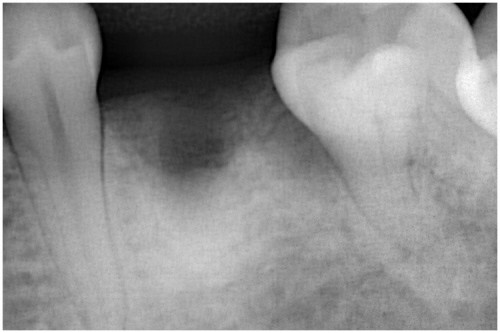

術前

抜歯後

埋入前(抜歯後約6ケ月)

上記、拡大写真

インプラント埋入直前

インプラント埋入時

同拡大

支台装着

被せ物装着

同全体写真